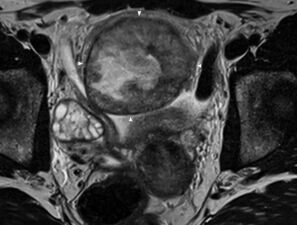

15-jähriges Mädchen mit subakutem Bauchschmerz und Infektzei...

Appendizitis, Ovarialtorsion, Urolithiasis, infinzierte Urachuszyste oder etwas anderes? Fallbericht einer seltenen Differenzialdiagnose. Ein Fall aus der Reihe "Der diagnostische Blick".